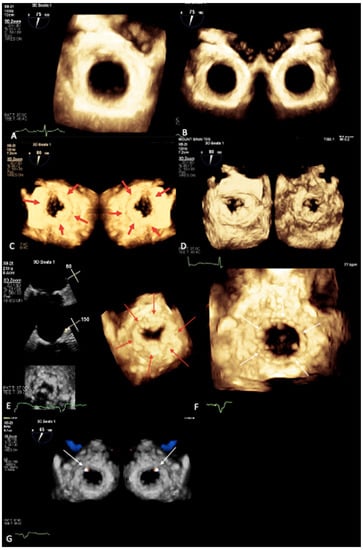

- Prandi, F.R.; Dangas, G.D.; Kini, A.; Romeo, F.; Suleman, S.; Khera, S.; Tang, G.H.; Sharma, S.; Lerakis, S. Intraprocedural Mapping of the Mitral Calcium for Positioning and Deployment of Transcatheter Valve-in-Mitral Annular Calcification. JACC Cardiovasc. Interv. 2022, 15, 2341–2343. [Google Scholar] [CrossRef] [PubMed]